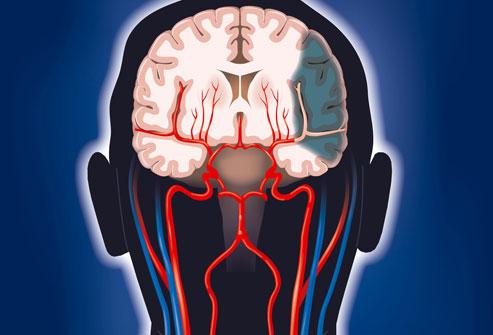

腦梗,即腦梗死,是一種由于腦部血液供應(yīng)障礙導(dǎo)致的局部腦組織缺血、缺氧,進而引起腦組織軟化及壞死,腦梗可分為腦血栓形成、腦栓塞和腔隙性梗死等多種類型。

腦梗是一種常見的腦血管疾病,具有高發(fā)病率、高致殘率和高死亡率的特點,腦梗是指局部腦組織因血液循環(huán)障礙,導(dǎo)致缺血、缺氧而發(fā)生的軟化壞死,本文將詳細介紹腦梗的各個方面,幫助讀者更好地認識這一疾病。